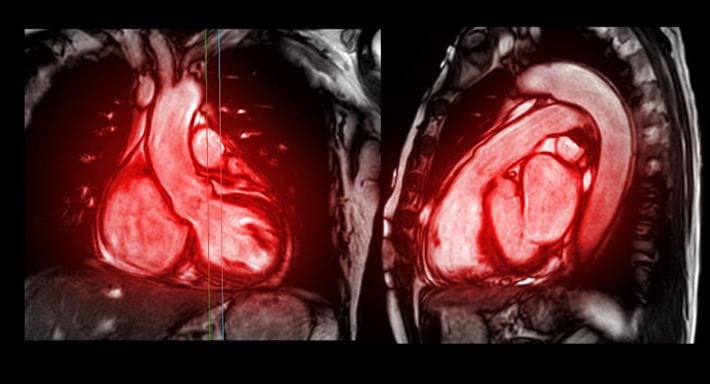

※写真はイメージです